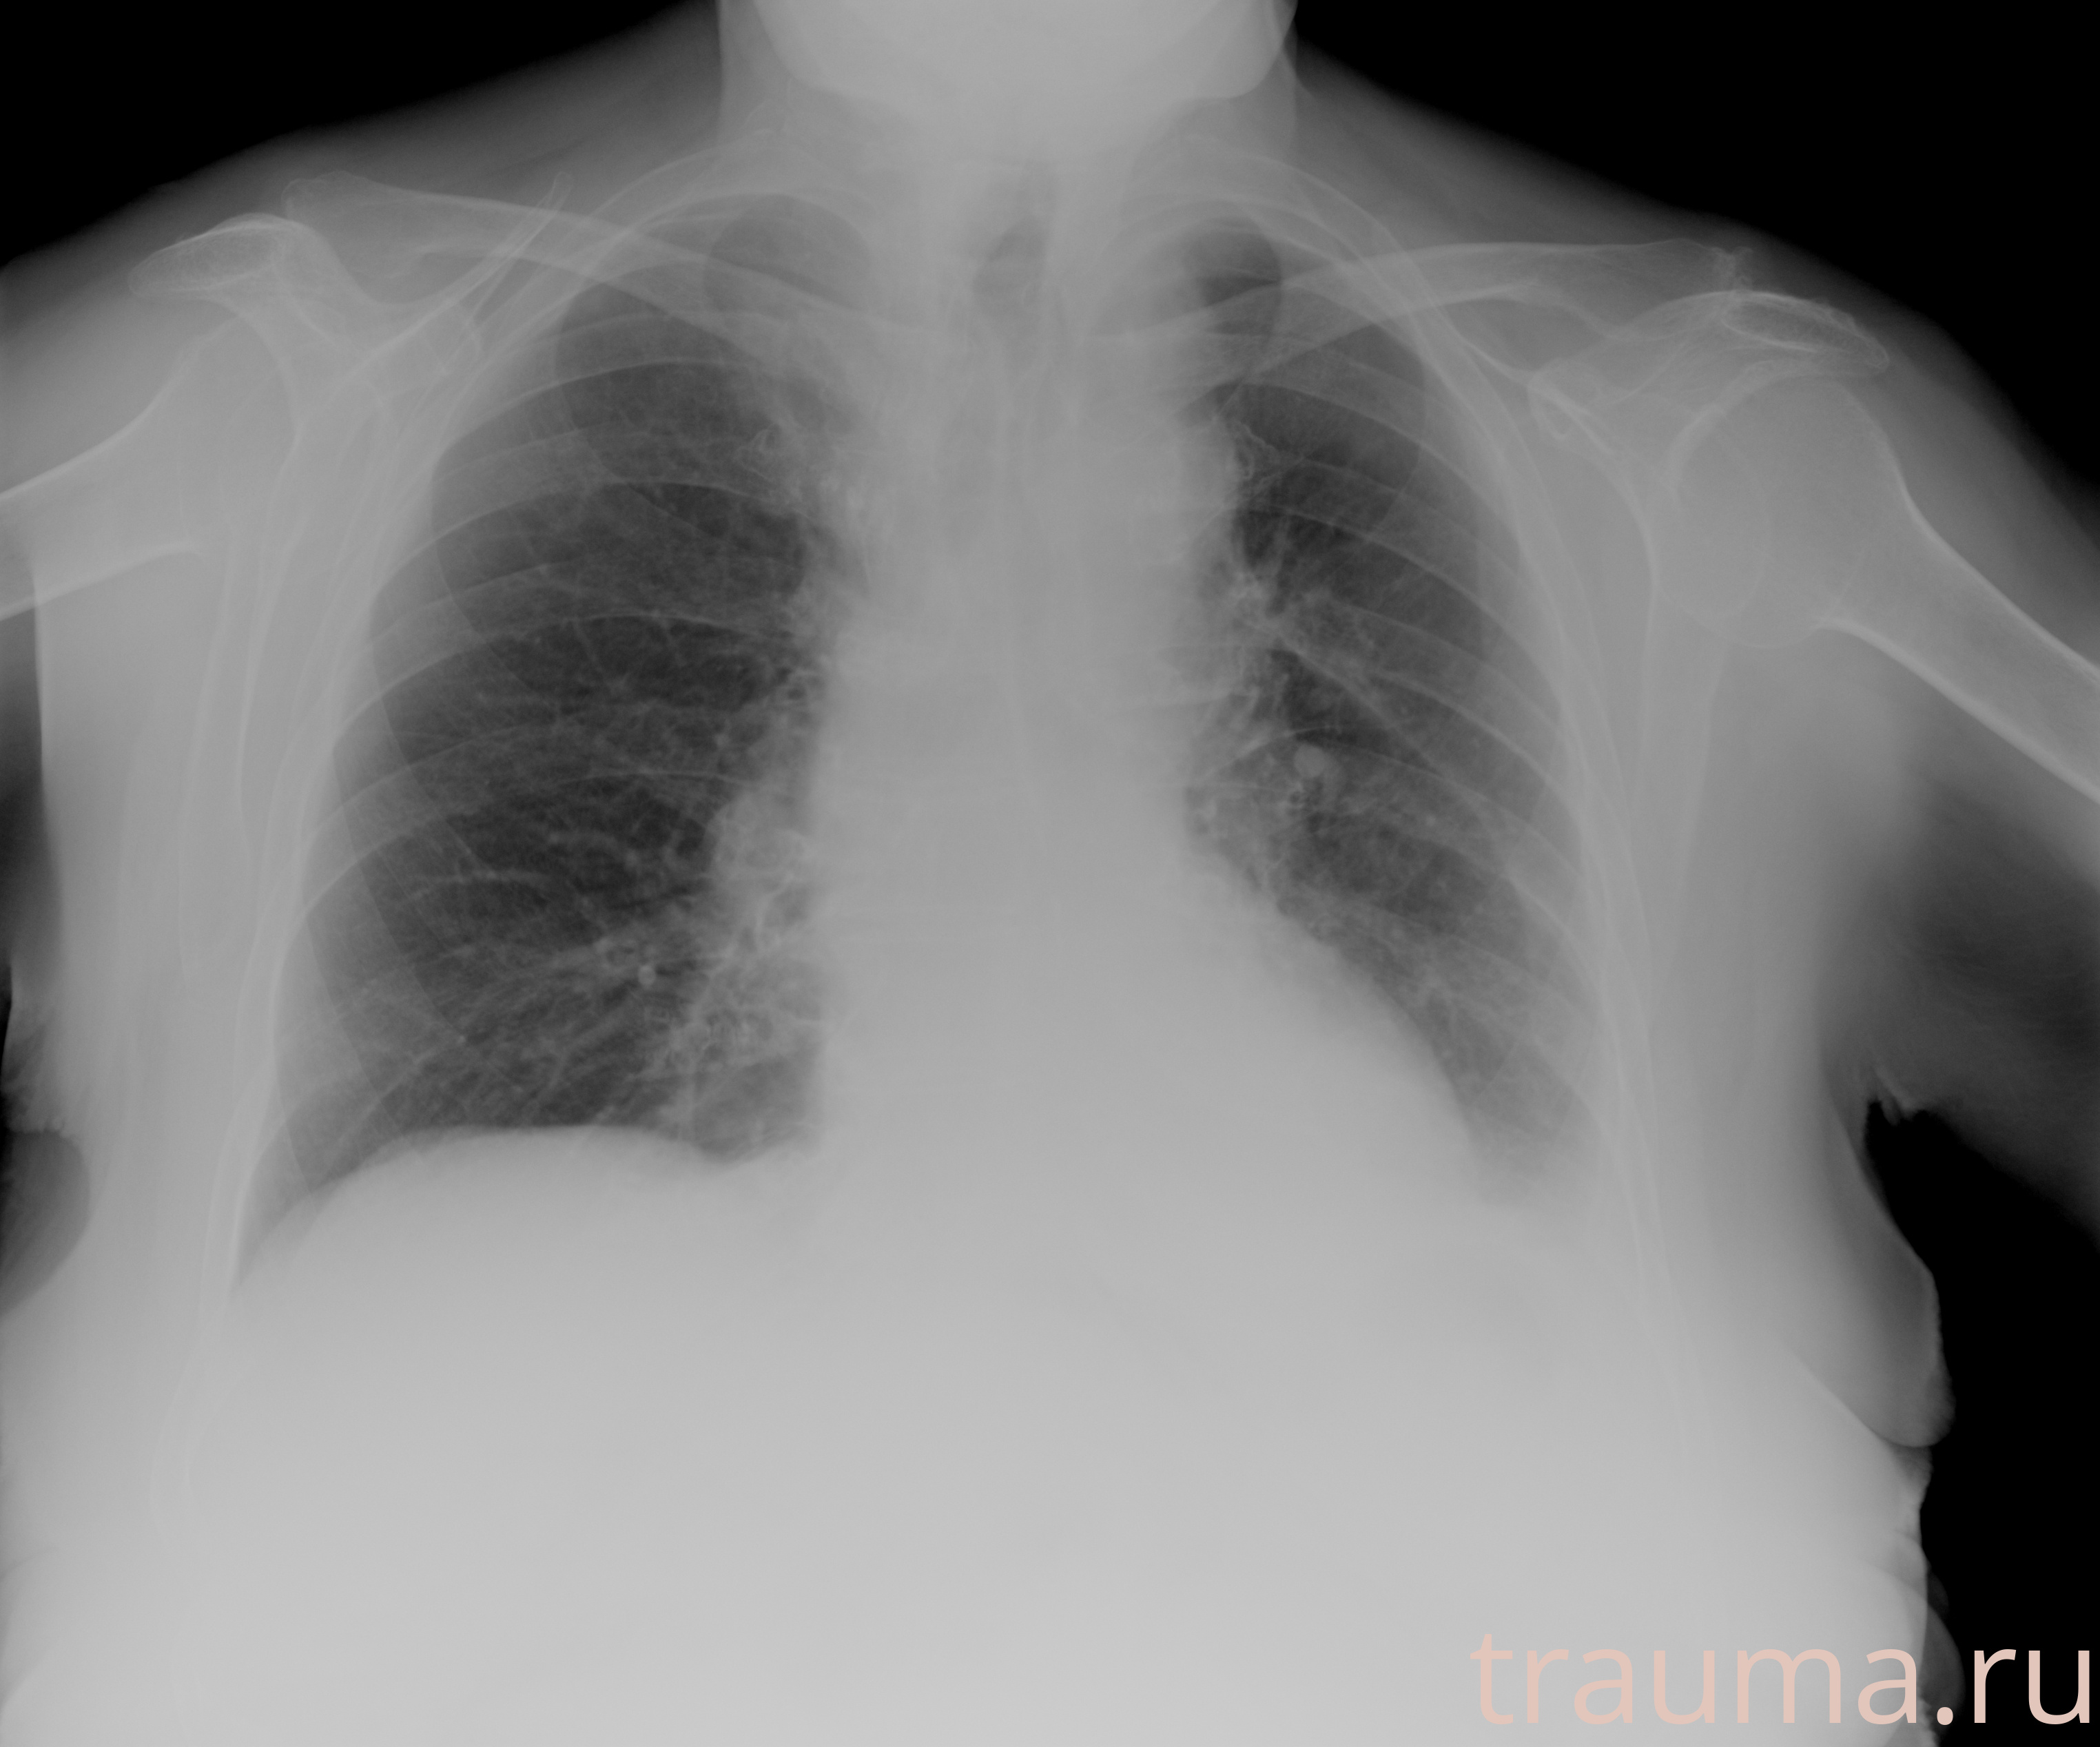

Рентгенограммы

Рентген на дому: по вашему адресу приезжает врач-рентгенолог, травматолог-ортопед с мобильным рентгеновским аппаратом, проводит диагностику травмы или заболевания, делает необходимые рентгенограммы, дает рекомендации по дальнейшему лечению. Получить качественные снимки в домашних условиях возможно благодаря уникальной методике, разработанной МосРентген Центром для института  Склифосовского

Яркость: 1   Контраст: 1   Инвертировать: 0 Увеличение: 1

Перетаскивайте мышь вверх/вниз для контраста, влево/право для яркости. Прокрутка колесом изменяет масштаб. Нажмите Сбросить для возврата к исходному изображению. При увеличении держите мышь в той области, которую хотите рассмотреть.